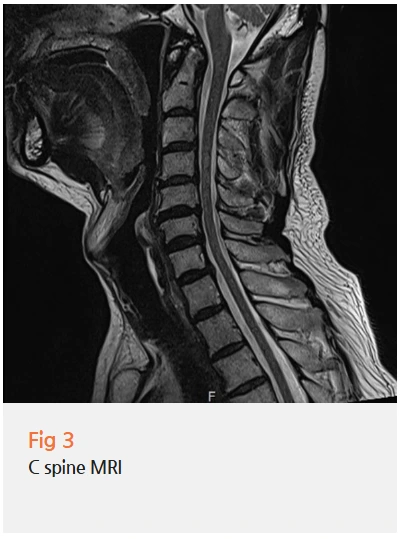

뇌 검사 결과를 보면서 저는 경추 쪽을 다시 꼼꼼하게 살펴봤습니다.

환자분에게는 경추 추간판탈출증과 경추 협착증이 동반되어 있었어요.

이게 귀 통증과 무슨 관계냐, 처음 들으시면 연결이 안 될 수 있습니다.

%EA%B7%B8%EB%A6%BC9.png?type=w966

해부학적으로 설명드리면 이렇습니다.

✔️ 후두부신경은 경추 상부에서 분지해 두피와 후두부, 귀 뒤쪽까지 이어집니다.

✔️ 대이개신경은 경추 2-3번에서 나와 귀 앞뒤, 볼 아래쪽까지 분포합니다.

즉, 목에서 나오는 신경이 귀 주변까지 연결되어 있다는 거예요.

경추에 협착이나 디스크 문제가 생기면, 이 신경들이 자극을 받아 귀 통증이나 안면 저림으로 나타날 수 있습니다.

이걸 대이개신경통, 후두신경통이라고 부릅니다.

이 환자분의 경우, 바로 이 경로에서 문제가 발생하고 있었어요.

귀 자체는 멀쩡한데 귀가 아픈 이유, 이렇게 설명이 되는 겁니다.